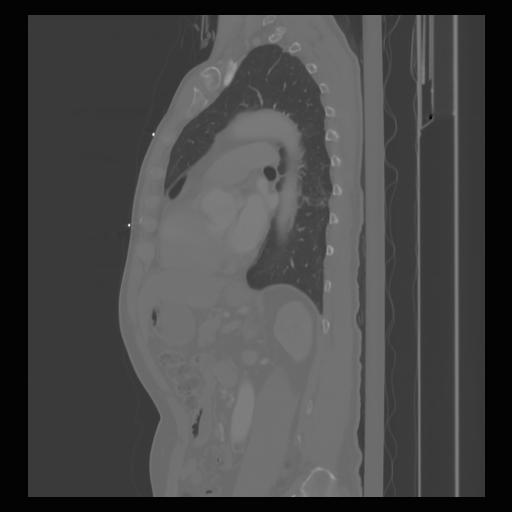

30 CUERPO,CE,Sagittal,3.000,CUERPO,Sagittal,